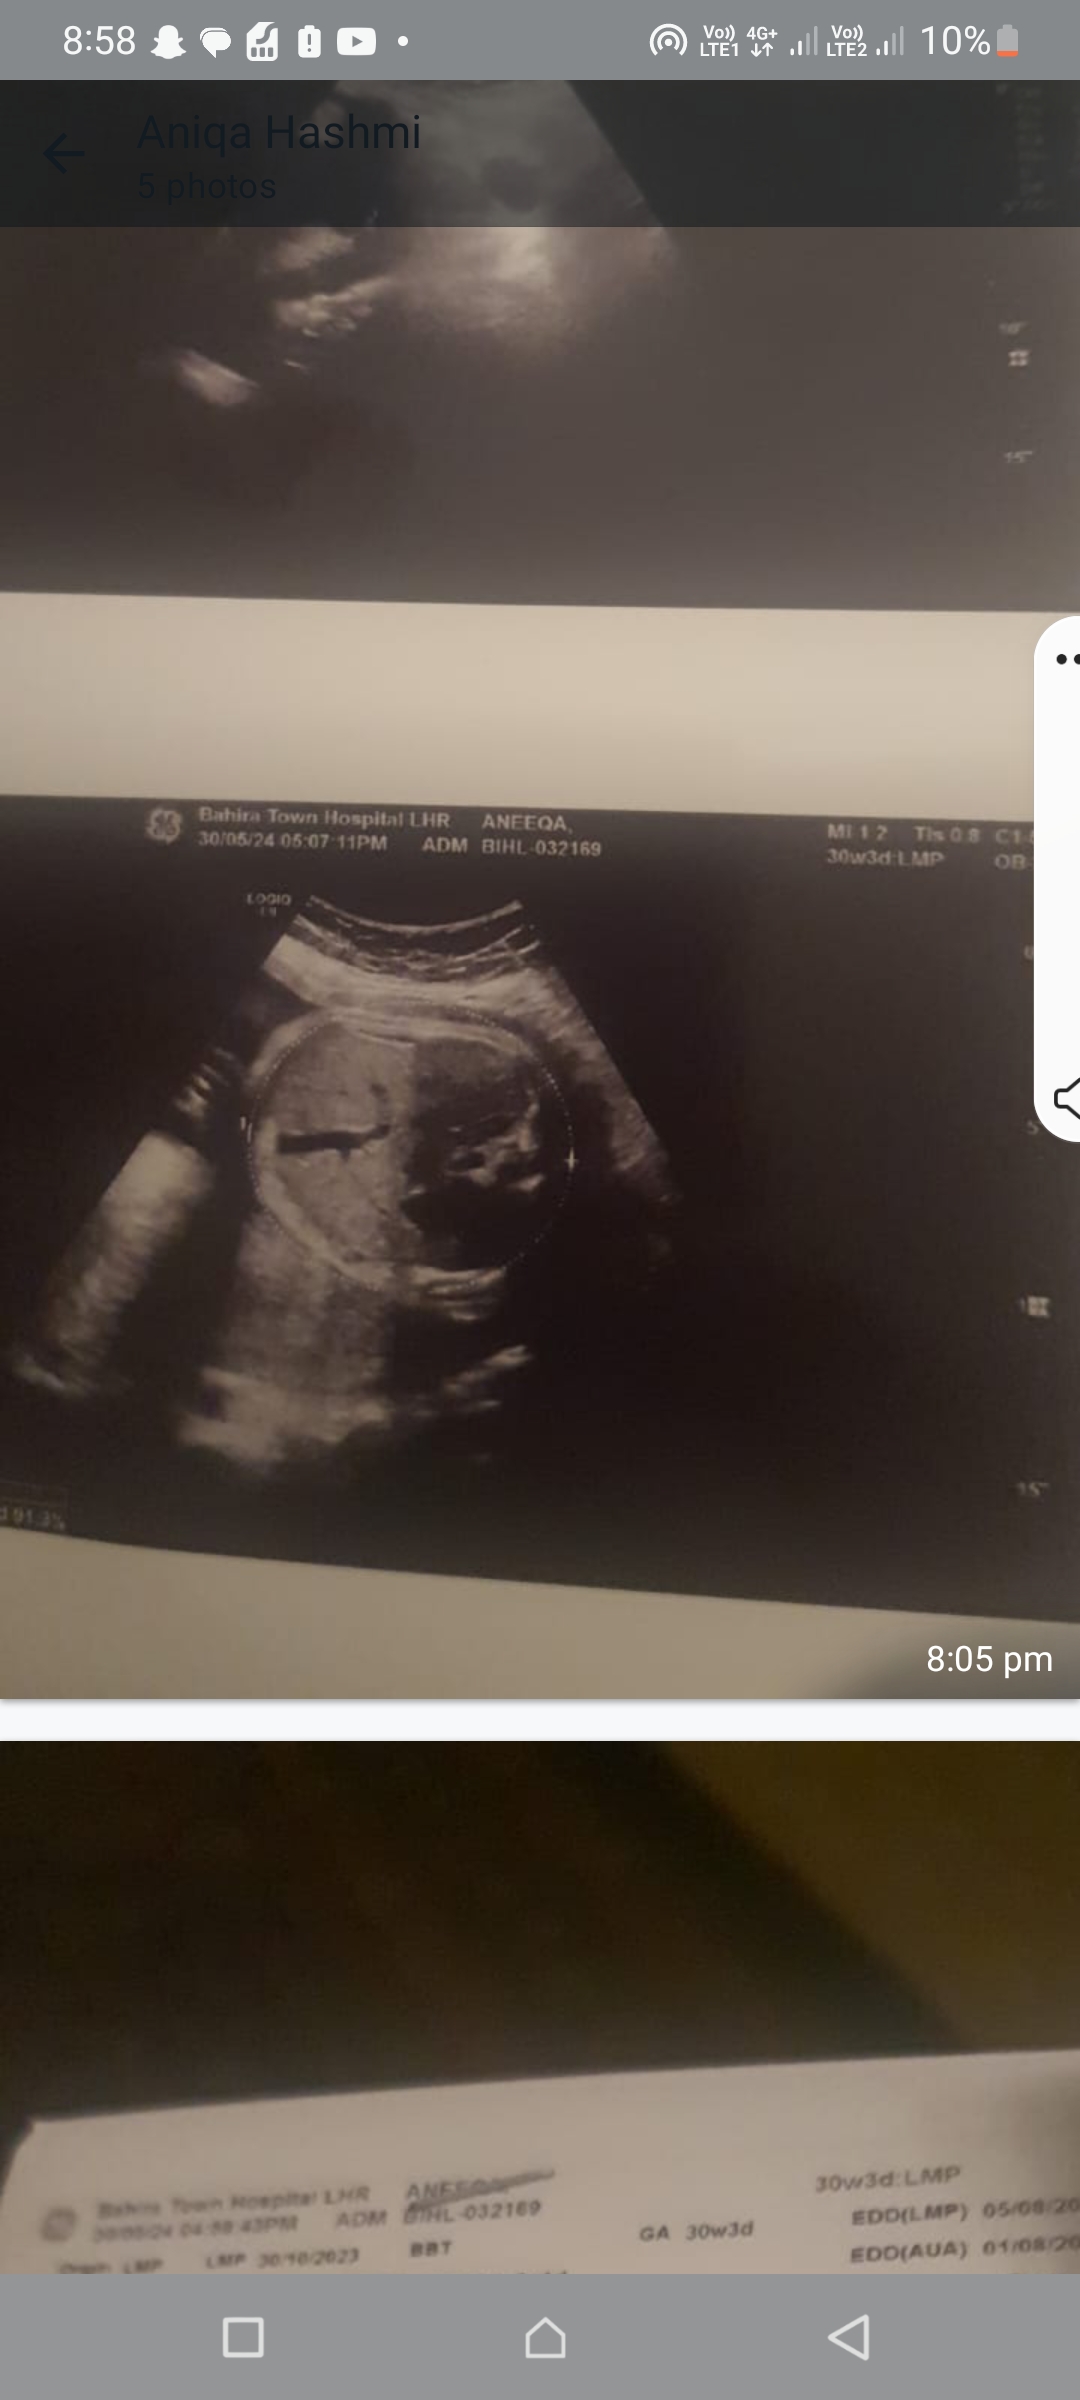

Please tell me about altrsound one tell ma about gender

Attach Photo here: